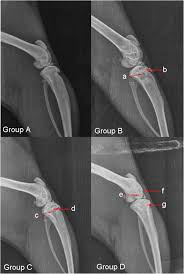

Representative Images Of Each Ossification Grade. White Arrows Indicate...  | Download Scientific Diagram

Representative Images Of Each Ossification Grade. White Arrows Indicate… | Download Scientific Diagram